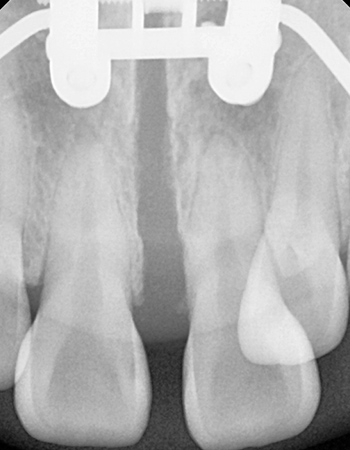

확장 후

이지민 원장은 성인 비발치 교정의 핵심인 비수술 악궁 확장 가능성을, 직접 연구한 논문 결과를 바탕으로 사전에 정밀 분석·예측합니다.